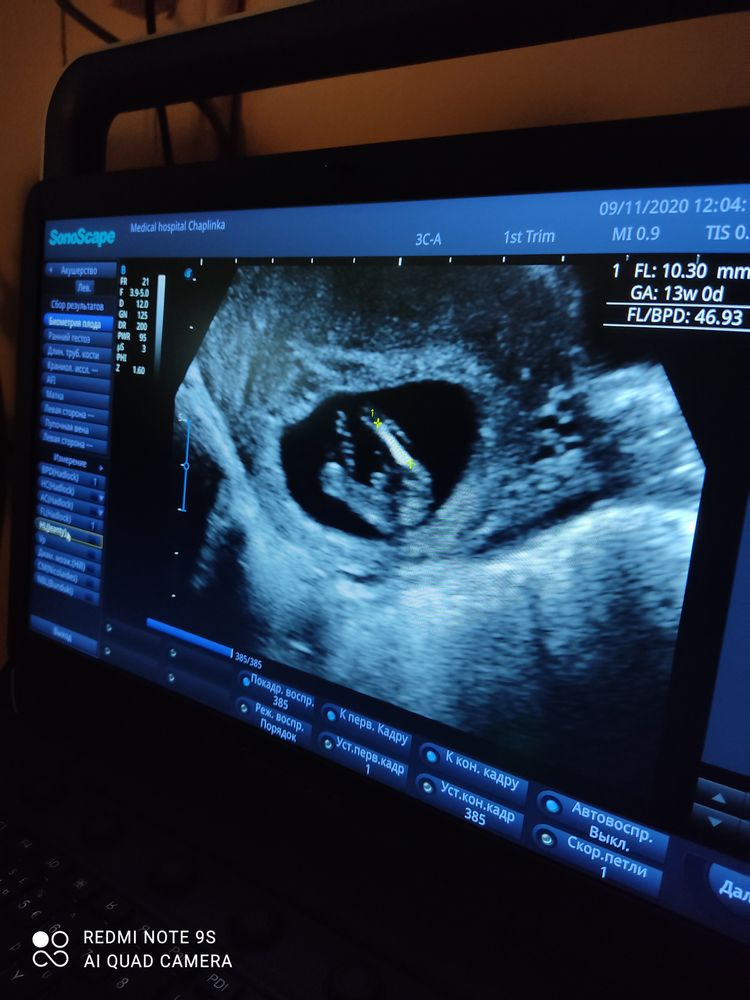

Мальчик???

На вашем сроке с этого ракурса у мальчиков и девочек все одинаково, надо сбоку смотреть.

Нет, в 14 недель уже чётко различимо, где мальчик, а где девочка.

Как по мне, то там девчачий пирожочек. Во вторую беременность тоже смотрели между ножек, а не по половому бугорку. Примерно такая же картина была.

Я вижу совершенно точно попец, а все остальное закрыто не пойму чем. В вашем случае как раз 50/50,но я б сказала 49 парень и 51 девочка. Яичек не видно

Не знаю, мне кажется мальчик)) где все увидели пирожок...не понимаю

На девочку похоже. Ибо не писюна, не машонки нет. И это пирожок

Пирожок девчачий 🧐

Сказали мальчик 🤐🤐🤐 ой посмотрим. )))

Слишком большой причиндал для такого срока 😀 Скорее всего какая-то другая часть тела. В 15 неделек уже будет видно пол на узи.